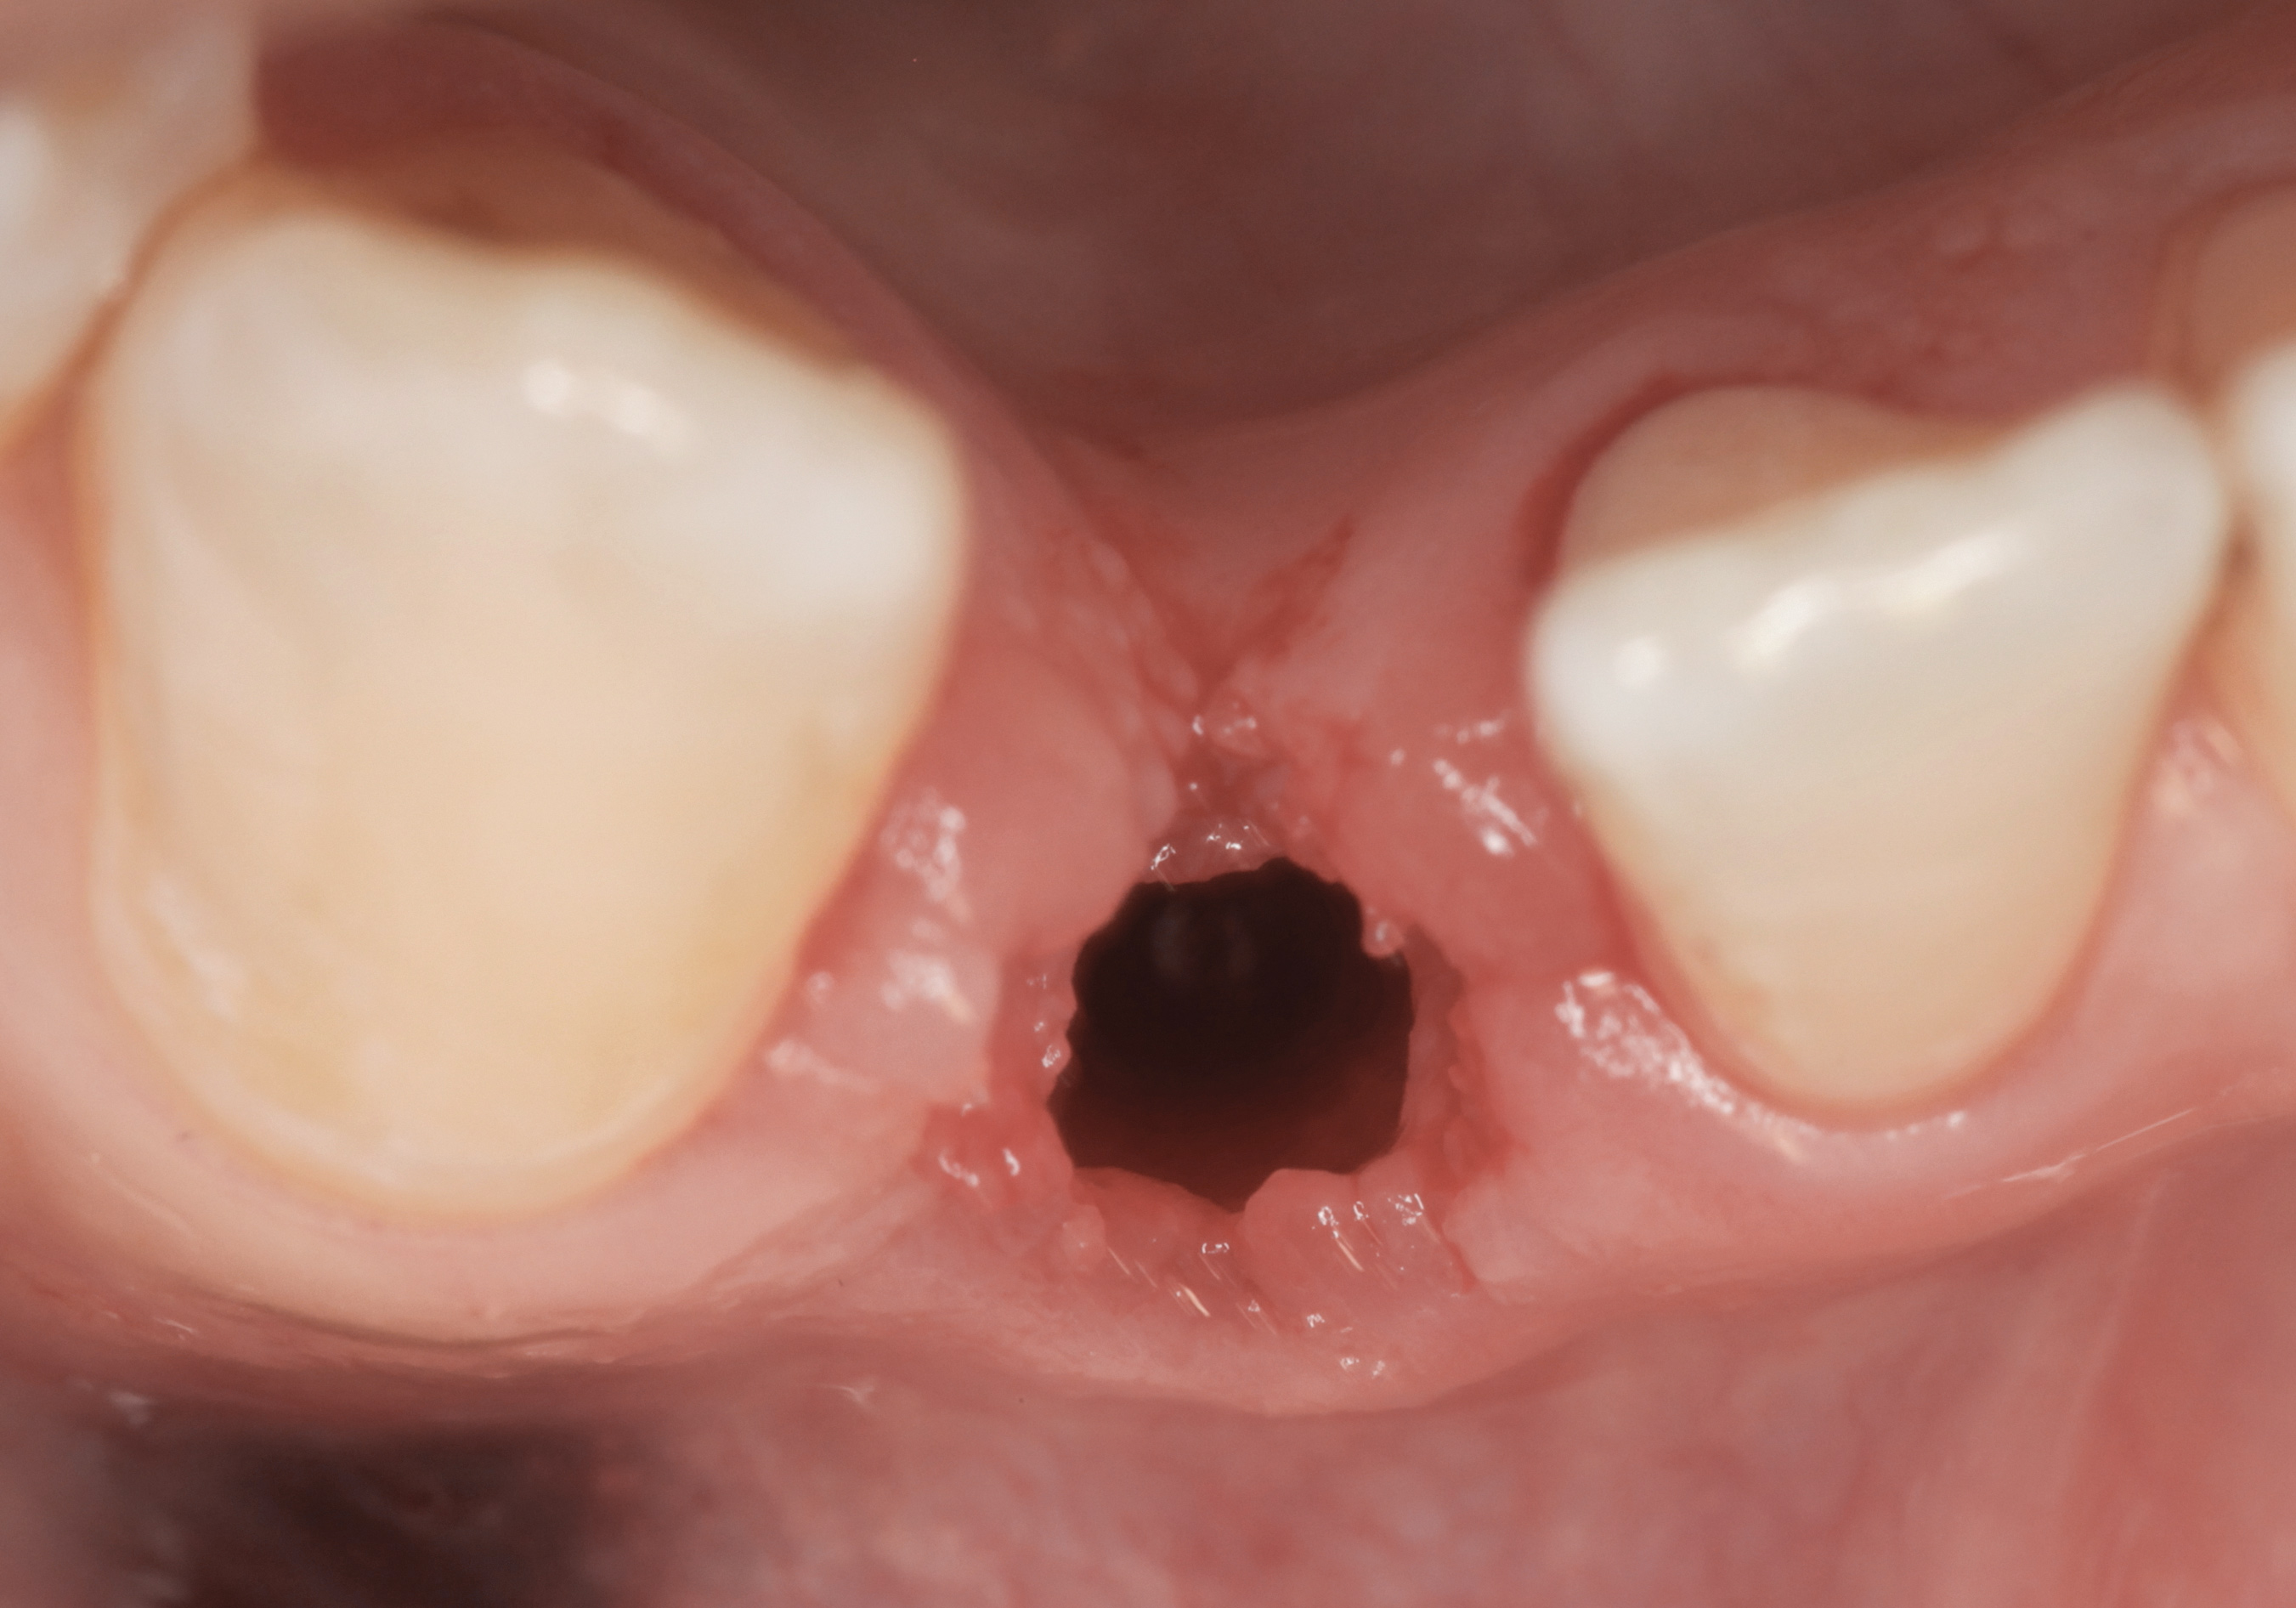

The crown and screw-retained custom abutment were removed, and a surgical cover screw was placed into the implant, thereby allowing spontaneous gingival augmentation in situ (Figure 33 and Figure 34). Note that the lingual aspect of the implant site was significantly more coronal than the labial aspect, which was positive because the defect would be limited to a facial–lingual defect. A fixed RBR bridge was cemented on the adjacent teeth and used as a tooth-supported transitional provisional restoration (Figure 35). A few weeks were allotted to let the soft tissue heal and migrate around the cover screw (Figure 36) to see if there would be complete coverage, thereby allowing a soft-tissue augmentation procedure to be performed with primary flap closure as in clinical scenario No. 2. The major obstacle in achieving a positive tissue response was that the implant depth was also deficient because the implant–abutment connection was at the level of the free gingival margin. It was decided that the best treatment option would be to remove the implant. A high-powered reverse-torque device (Fixture Remover Kit, NeoBiotech, www.neobiotechus.com) was used to remove the implant atraumatically (Figure 38 through Figure 41). The implant socket was allowed to heal for several months not unlike an extracted tooth (Figure 42). A new implant was placed in a better position from both a restorative and esthetic perspective (Figure 43), and after a few months of healing, a new crown was made (Figure 44). A satisfactory functional and esthetic result was achieved (Figure 45 and Figure 46) without employing pink porcelain.

Fig 38. A reverse-torque screw was placed into the implant.

Figure 38

Fig 39. A counter-torque device was placed over the reverse-torque screw.

Figure 39

Fig 40. The implant was easily unscrewed within minutes in a minimally invasive manner with less trauma to the surgical site.

Figure 40

Fig 41. The removed implant with some apical bone adherent to the surface.